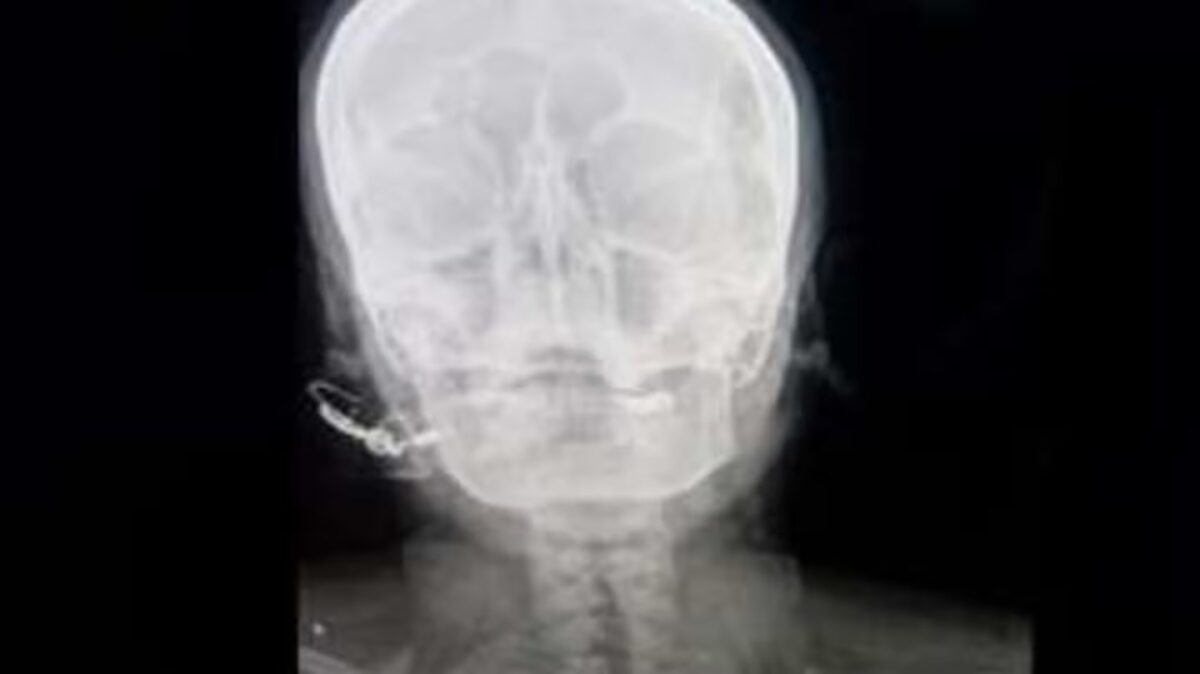

“Estaba totalmente consciente, pero sufría mucho”, indicó el galeno. Una radiografía confirmó que el clavo había sido introducido cinco centímetros en su cráneo, aunque no alcanzó el cerebro. La mujer, madre de tres hijas, afirmó estar embarazada de una cuarta niña.